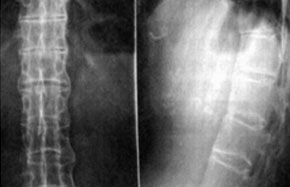

济南强直性脊柱炎研究所科室诊疗

打造强直性脊柱炎规范化临床知识库特色技术